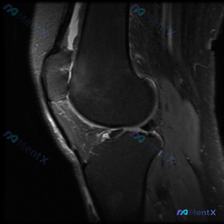

看到一份很有启发的膝关节MRI读片资料,整理出来和大家分享一下,这个病例其实很能体现读片的时候不要被初始印象带偏的思路。 基本影像信息 这是一张膝关节矢状位T2加权MRI图像,图像质量良好,解剖结构显示清晰,没有明显运动伪影,可以满足诊断分析需求。图像上可以清晰识别股骨远端、胫骨近端、髌骨、髌韧带、...

看到这张膝关节MRI矢状位T2序列的影像,整理一下分析思路,和大家一起讨论。 先整理影像核心发现 这是单张膝关节MRI矢状位T2序列影像,核心异常如下: 1. 骨骼结构:股骨远端、胫骨近端、髌骨轮廓完整,无明显骨皮质断裂 2. 韧带:前交叉韧带(ACL)走行可见,但近股骨附着点和中段低信号连续性不佳...